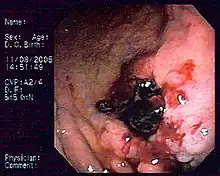

| Endoscopic image of gastric MALT lymphoma taken in body of stomach in patient who presented with upper GI hemorrhage. Appearance is similar to gastric ulcer with adherent blood clot. | |